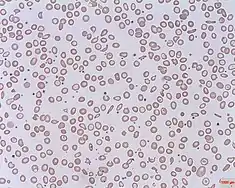

Unconjugated hyperbilirubinemia arises before bilirubin reaches the liver as liver conjugation capacity is overwhelmed in haemolytic anaemias, in which red blood cells are disproportionately destroyed, leading to excessive haem metabolism thus bilirubin production.[6] This may stem from hereditary spherocytosis, a congenital disease characterized by abnormally sphere-shaped erythrocytes, rendering erythrocytes prone to degradation.[18] Other causes include enzyme irregularities like G6PD deficiency that produce unusually structured haemoglobins.[18]

Serum tests evaluate plasma bilirubin, haemolysis and liver function and are essential for definitive diagnosis. When total serum bilirubin exceeds 2.5 mg/dL and unconjugated bilirubin occupies >85% of total amount, it is classified as unconjugated hyperbilirubinemia.[6] A complete blood cell count illustrating decreased fraction of intact erythrocytes signifies haemolysis, hinting for haemolytic diseases.[4] Other than haemolysis, hepatocellular injury suggestive of liver diseases like hepatitis can be inferred through increased plasma concentration of aminotransferases AST and ALT, enzyme markers of liver function.[7]